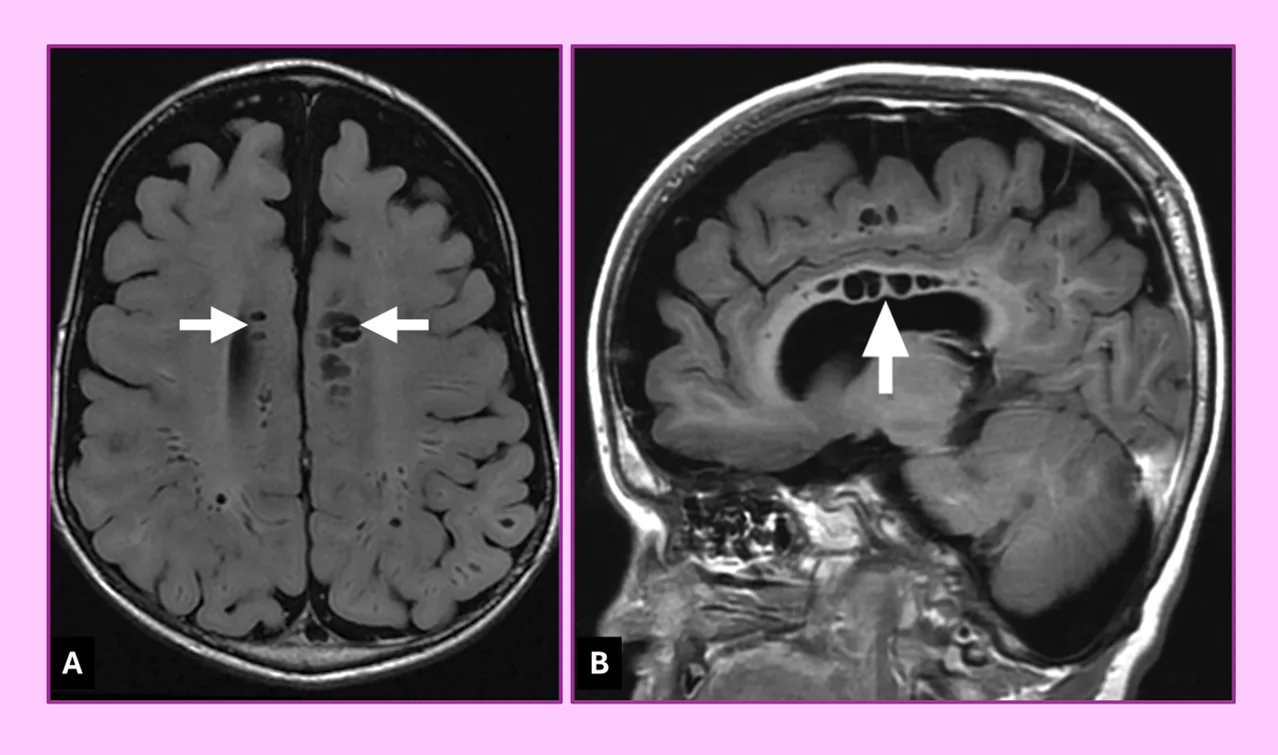

Наконец-то я увидел это воочию! Киста полости Верги, промежуточного паруса, осложнённая гидроцефалией. Из анамнеза: Низкое артериальнео давление, нарушение речи, затуманенное сознание, головная боль, головокружение, в 1989 году перенёс менингит.

А Вы видали такое? Я впервые вижу, раньше только читал в литературе.